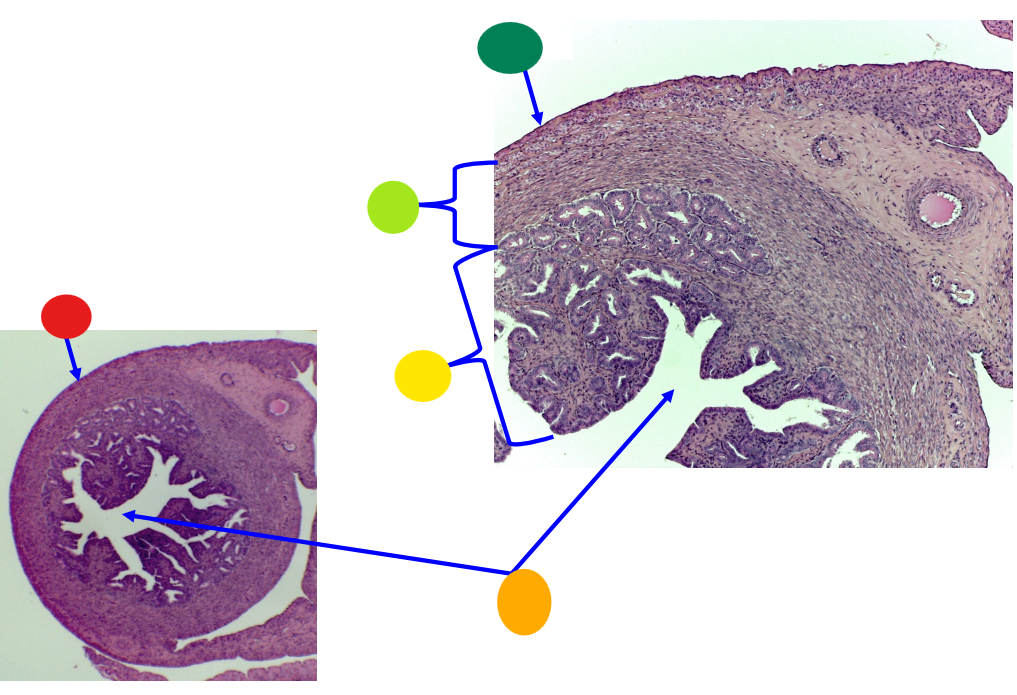

red

primary oocyte

orange

zona pellucida

yellow

granulosa cells

light green

developing thecal cells

What is this

secondary follicle

red

granulosa cells

orange

primary or secondary oocyte

yellow

oocyte nucleus

light green

zona pellucida

dark green

cumulus oophorus

light blue

antrum

dark blue

thecal cells

what is this

tertiary follicle